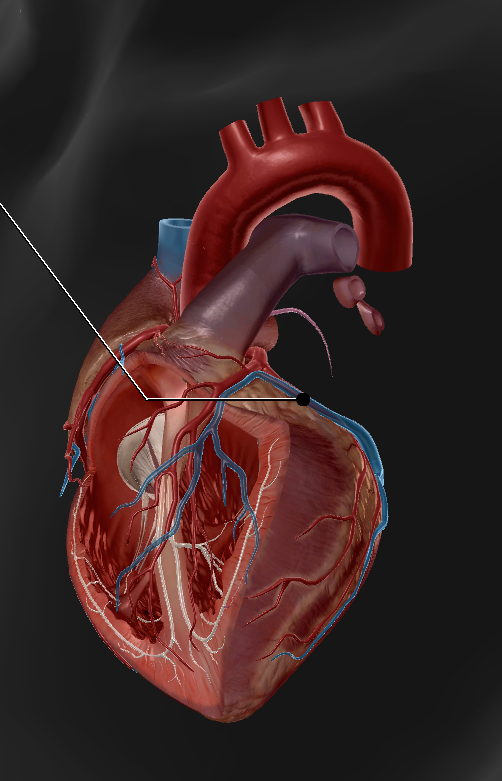

Anterior Interventricular Artery

Circumflex Branch

Coronary Artery

Middle Cardiac Vein

Coronary Sinus

Anterior Interventricular Sulcus

Coronary Sulcus

Small Cardiac Vein

Anterior Cardiac Vein

Posterior Interventricular Sulcus/Artery

Coronary Veins

Marginal Branch

Circumflex Artery

Great Cardiac Vein